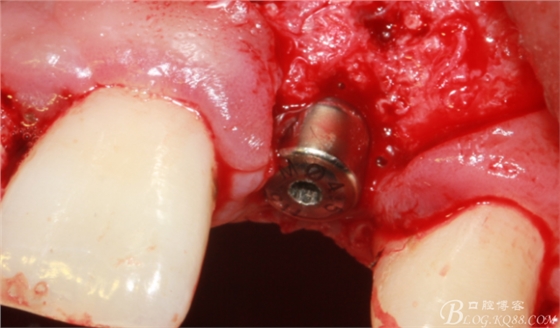

順利植入植體,扭力30N。三壁骨,感覺美美的。

刮自體骨覆蓋種植體表面。

血液調(diào)扮BIO-OSS骨粉覆蓋術(shù)區(qū)。

蓋生物膜,固定。